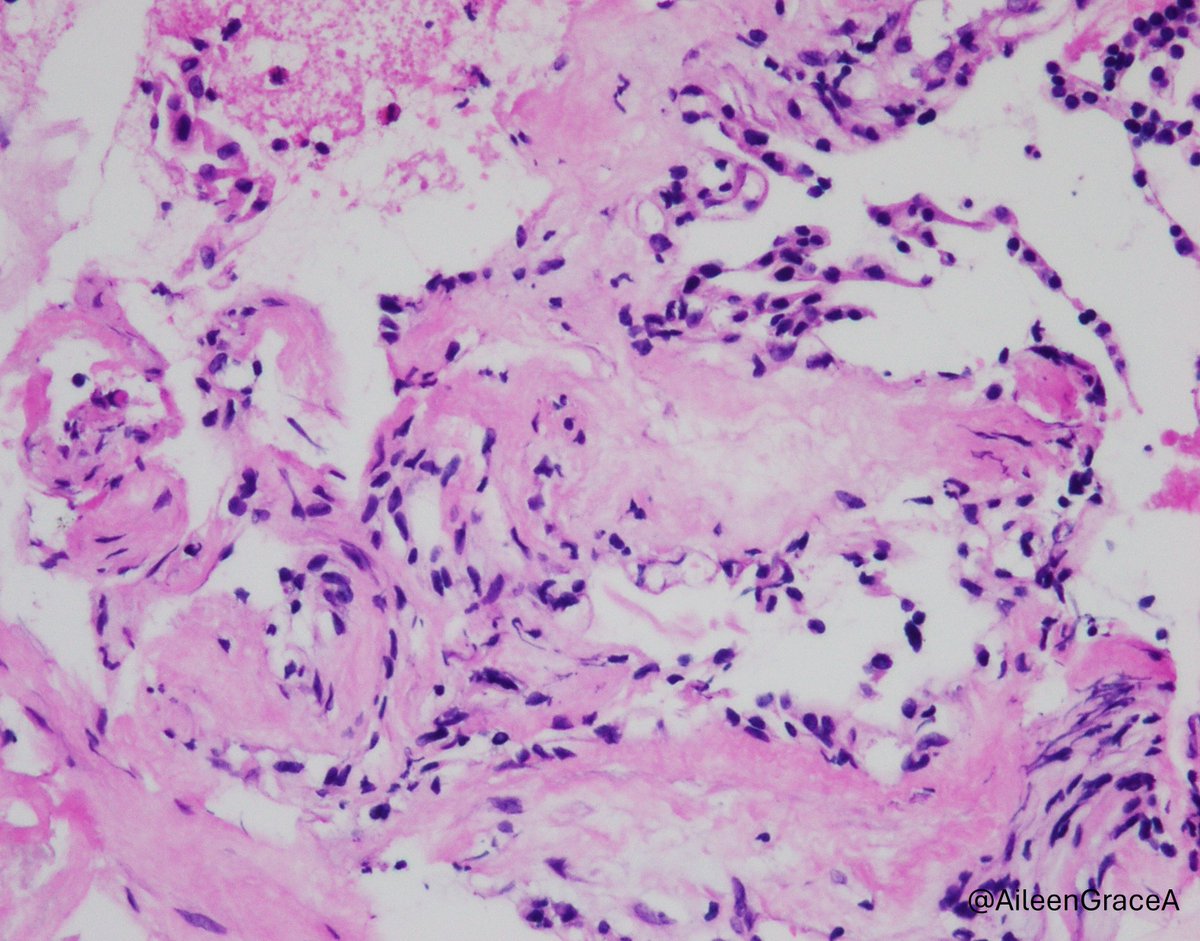

Atypical polypoid adenomyoma: biphasic lesion with crowded, architecturally complex endometrioid glands showing cytologic atypia, embedded in a myomatous stroma. Don’t overcall as carcinoma #PathTwitter #GYNpath